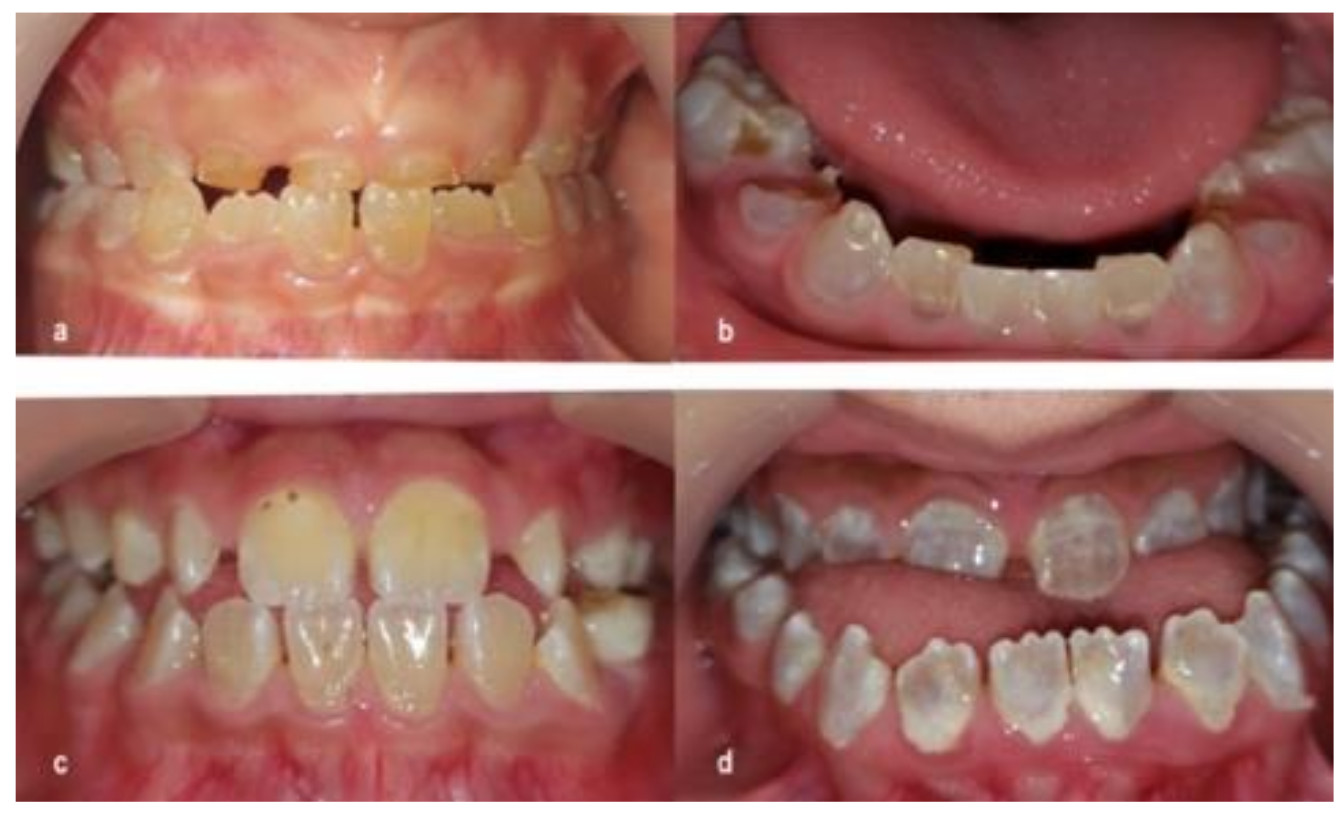

3.1. Dentinogenesis Imperfecta

3.2. Caries

4.1. Dentinogenesis Imperfecta

4.2. Caries